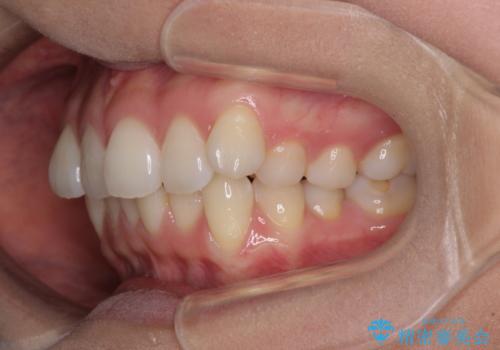

- 前歯のデコボコを治したいとのことで来院された患者様です。

上下顎ともに歯列全体の後方移動とIPR(歯と歯の間を削る)によってデコボコが解消するように設計し、インビザラインにより治療を行うこととしました。

上下ともにIPRを積極的に行っているため、舌の突出癖をしっかりと改善できないと、後戻りにより隙間やデコボコが早い段階で発現することになるため、舌のトレーニングが非常に大切になります。